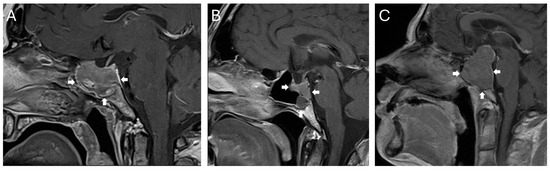

A total of 557 surgeries for pituitary neuroendocrine tumors in an endonasal endoscopic transsphenoidal technique performed between 1 January 2015 and 31 August 2025 at the Department for Neurosurgery at Ulm University, Germany, were reviewed, and 13 cases (2.3%) were identified with predominantly sellar or infrasellar growth and extension into the clivus. Giant adenomas with diffuse infiltration into the clivus but also all other areas of tumor circumference were not included (for examples of tumors primarily extending below the sella, see Figure 1). Due to the often highly irregular and nodular suprasellar tumor growth, volumetry was not used to qualify the tumor as primarily extending below the sella and into the clivus. To qualify for an inclusion, more than 50% of the tumor mass was required to be within and below the sella, with only minor suprasellar nodules in relation to the tumor mass.

Figure 1. Examples of lesions included in this retrospective study. All lesions showed predominantly a growth from the sella into the clivus. While some tumors only spread from the sella inferiorly (A,B), others also demonstrated a minor growth into the suprasellar region (C). Infiltration of the sphenoid sinus is present in all three examples. The tumor extension is highlighted by white arrows.